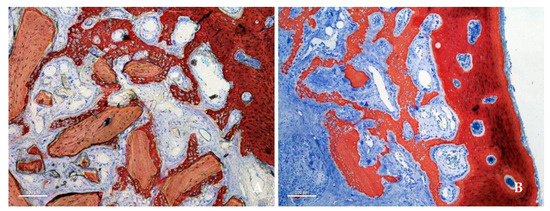

3. Results